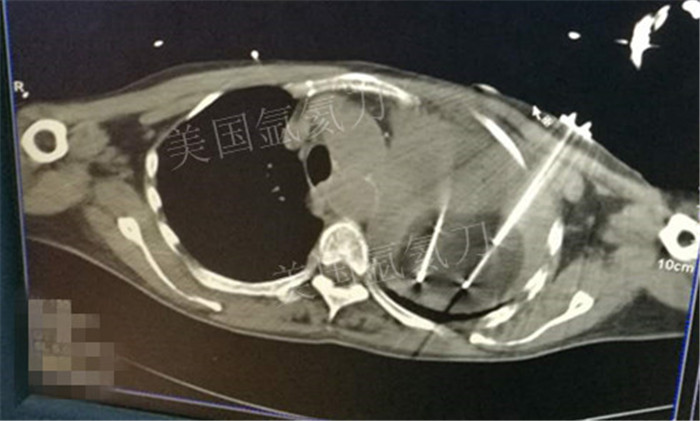

下一篇:氩氦冷冻治疗最大径8.2肿瘤,冰球最大径7.9